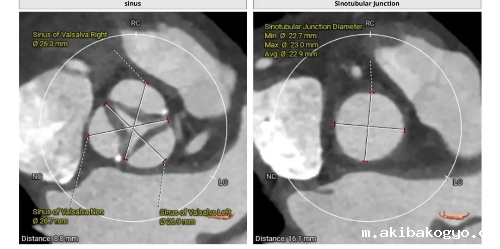

曾阿姨术前评估:法式窦结构不大;STJ:高度16.1mm,直径22.9mm